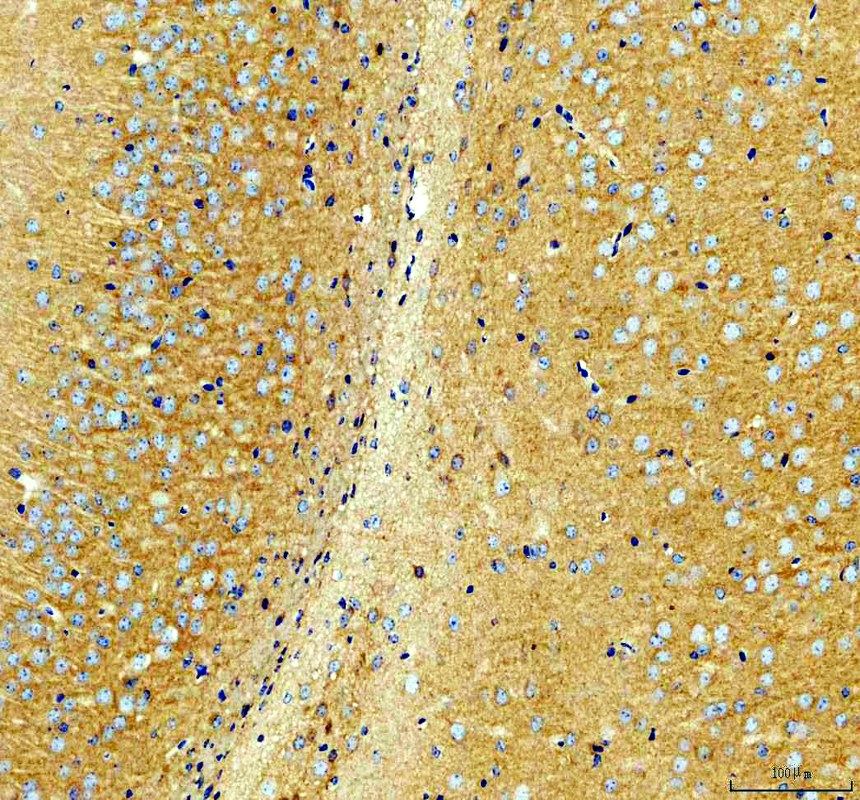

IHC analysis of NMDAR2B/GRIN2B using anti-NMDAR2B/GRIN2B antibody (A01883-2).

NMDAR2B/GRIN2B was detected in a paraffin-embedded section of rat brain tissue. The tissue section was incubated with rabbit anti-NMDAR2B/GRIN2B Antibody (A01883-2) at a dilution of 1:200 and developed using HRP Conjugated Rabbit IgG Super Vision Assay Kit (Catalog # SV0002) with DAB (Catalog # AR1027) as the chromogen.